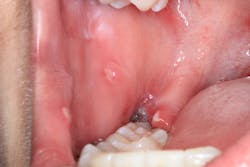

Clinical assessment revealed multiple white lesions with red borders salt-and-peppered in a generalized fashion throughout the entire oral cavity. The gum tissues were swollen and any light palpation/touching of the lesions resulted in bleeding and pain. See clinical photos below.